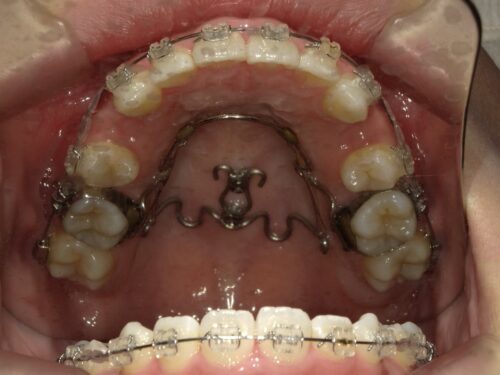

ワイヤー装着後・上顎の写真

上顎に装置とスクリューが装着された状態

上の前から4番目の歯を抜歯し、上顎に入れたスクリューとワイヤーを繋いで、前歯を後ろに引っ張っていきます。これが今回の治療のポイントになります。